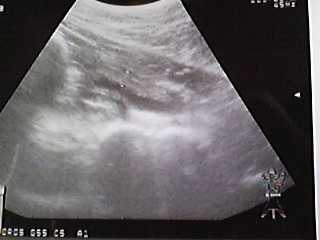

=====膀胱のエコー写真=====

① 11月2日

真ん中の黒い部分がオシッコ

上部の白い部分に炎症3~4mm